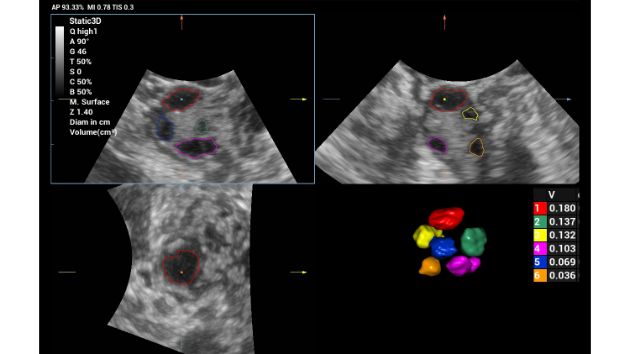

Smart FLC automatically detects the number of follicles and calculates each volume from a 3D ovarian volume image, assuring accurate assessment of follicles, essential for IVF exams.

Consona Series Women Health Solution - Smart FLC feature image

Ovary 2D

Ovary Color